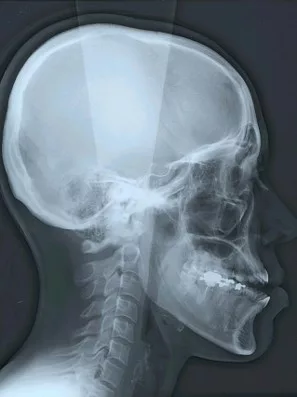

Parmi les examens radiographiques nécessaires, les radiographies de profil et de face correctement orientées et contenant l’ensemble de la tête (sommet du crâne inclus) sont particulièrement importantes. Ces radiographies correctement effectuées permettent d’établir une véritable cartographie du squelette du patient et en conséquence de comprendre sa malformation. Cette analyse cartographique du squelette a pour nom « céphalométrie ». De nombreux types d’analyses céphalométriques existent et sont utilisées selon les pays et universités. Parmi elles, l’analyse céphalométrique architecturale et structurale de Jean Delaire tient une place particulière.

L’Analyse Céphalométrique architecturale et structurale de Jean Delaire

L’analyse céphalométrique architecturale crânio-faciale de Jean Delaire, à la différence des autres méthodes d’analyse qui sont principalement basées sur des moyennes statistiques définissant ce qui est « normal » et ce qui est « anormal » (c’est à dire pathologique) est basée sur la notion d’équilibre ou de déséquilibre architectural du squelette crânio-facial propre à chaque individu en tenant compte des principaux appareils anatomiques à son contact et des principales fonctions qui interfèrent avec lui. « A l’état d’équilibre, tous les éléments de l’extrémité céphalique ; squelette et tissus mous sont et fonctionnent en parfait équilibre mutuel ».

Pour chaque individu, l’analyse architecturale crânio-faciale de Jean Delaire permet de déterminer « l’équilibre » squelettique idéal qui lui est propre c’est-à-dire « sa normalité » et de constater, s’il existe, l’état de «déséquilibre » dans lequel il se trouve, c’est-à-dire l’état « pathologique » dans lequel il se trouve en tenant compte de son âge, de ses antécédents personnels ou familiaux, de son état fonctionnel ou dysfonctionnel, de l’existence d’éventuelles pathologies associées.

Pour chaque patient étudié l’analyse céphalométrique de Jean Delaire permet de :

- Connaître et de quantifier le morphotype qui lui est propre

- Analyser la situation d’équilibre (la normalité) ou de déséquilibre (la situation pathologique) dans laquelle se trouve l’ensemble de son extrémité céphalique ; crâne, massif facial et rachis cervical (analyse architecturale),

- Déterminer la participation respective de chaque élément anatomique dans la malformation ; maxillaire, mandibule, os basal, os alvéolaire, dents (analyse orthognathique et dentaire),

- Evaluer l’anomalie de position de chacune des pièces et unités anatomiques et de connaitre la position qu’elles auraient dû avoir en l’absence de pathologie guidant ainsi au mieux le chirurgien dans son plan de traitement chirurgical (analyse topographique)

L’analyse architecturale est complétée par l’analyse structurale. Pour chaque patient elle consiste à examiner attentivement tous la « structure » de l’extrémité céphalique c’est dire l’anatomie de chacune des pièces squelettiques et des parties molles qui la compose pour mieux comprendre le mécanisme d’installation et d’entretien de la dysmorphose. En association avec l’analyse architecturale elle permet de poser le diagnostic le plus précis afin de choisir le meilleur traitement chirurgical et orthodontique.

Analyse céphalométrique d’une sujet orthofrontal, orthognathe, à l’état d’équilibre en Classe I squelettique et dentaire (Schéma original Jean Delaire)